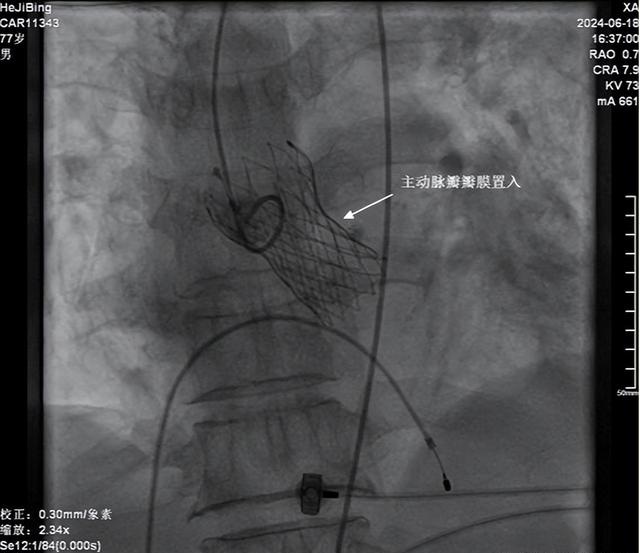

该手术经股动脉穿刺,球囊扩张狭窄的主动脉瓣后,经导管植入主动脉瓣膜支架,相比外科开胸手术,创伤小,感染风险小,恢复快,特别适合高龄、有基础疾病患者,且疗效确切。

这是一种微创介入导管技术。手术医生将带有人工瓣膜的导管通过血管(通常是腹股沟处的股动脉),推进到主动脉瓣的区域,在处于适当位置时导管缓慢释放,此时人工瓣膜被打开并开始起作用。

与传统开胸置换瓣膜手术相比,TAVR术无需开胸,创口小,手术时间短,术后感染风险更低,康复快,避免了心脏停跳和体外循环(体外循环血液灌注引起的各器官损伤不可避免),且由于TAVR的特点,手术在局部麻醉下即可完成,为无法接受传统开胸手术患者提供了一种新的治疗手段。